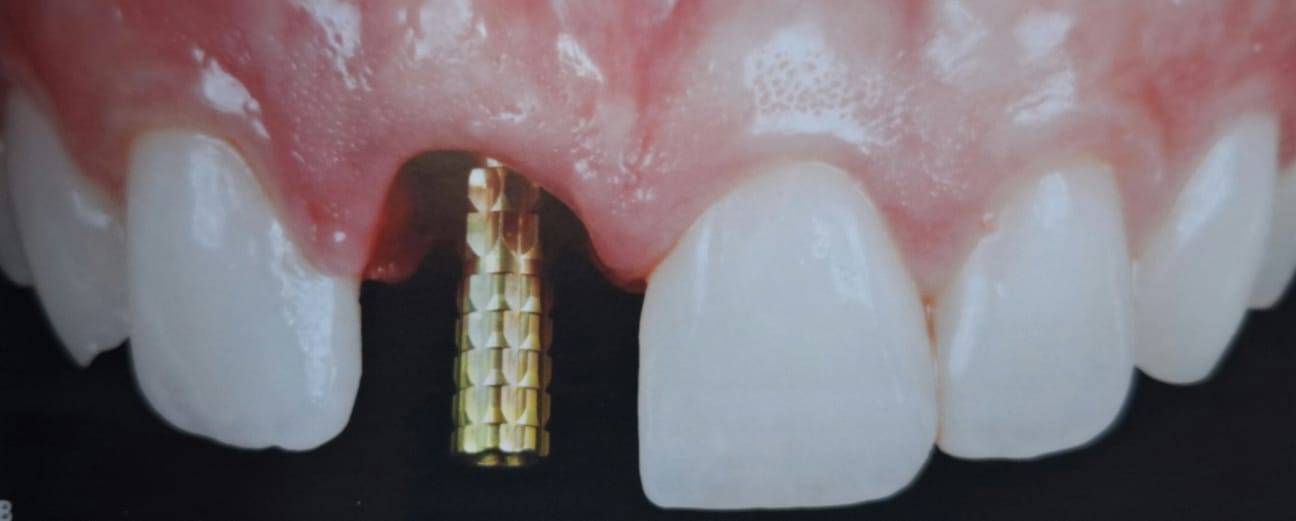

Veja aqui como são os novos critérios quantitativos que mudam a percepção da estética na prótese unitária sobre implantes.